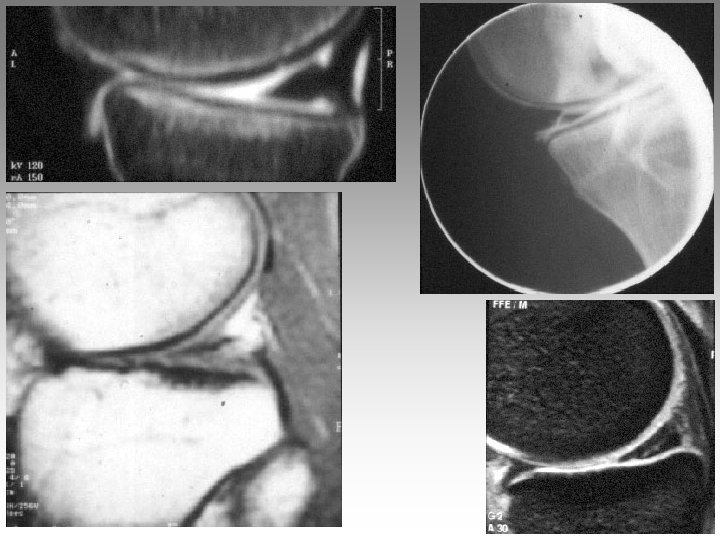

Hanche, T. , fract. fatigue Tendinites bursites, radic. Genou douloureux non traumatique Sémiologie Ponction +++ mécanique inflammatoire Rx inflammation Rx N Rx a. N < 40 ans interligne pincé Arthrose FT - FP contexte +++ > 40 ans Biologie, BS, Rx, IRM, écho interligne normal IRM AND, FF Paget, HOV ONA, OAN OAPH Ostéochond. infection IRM Arthroscopie Scinti. Os. LC Ménisque Coagul. PR, RP, Still, LED, SA…. Goutte, CCA AND ONA Ostéochondrite Pyogène, BK, Gono. , autres Hydarthrose X? Ostéochondromatose Synonite VN, T. , coag.

Genou douloureux non traumatique Sémiologie Ponction +++ mécanique inflammatoire Rx inflammation Rx N Rx a. N < 40 ans interligne pincé Arthrose FT - FP contexte +++ > 40 ans Biologie, BS, Rx, IRM, écho interligne normal IRM AND, FF Paget, HOV ONA, OAN OAPH Ostéochond. infection IRM Arthroscopie Scinti. Os. LC Ménisque Coagul. PR, RP, Still, LED, SA…. Goutte, CCA AND ONA Ostéochondrite Pyogène, BK, Gono. , autres Hydarthrose X? Ostéochondromatose Synonite VN, T. , coag.

Genou douloureux non traumatique Sémiologie Ponction +++ mécanique inflammatoire Rx inflammation Rx N Rx a. N < 40 ans interligne pincé Arthrose FT - FP contexte +++ > 40 ans interligne normal IRM AND, FF Paget, HOV ONA, OAN OAPH infection Biologie, BS, Rx, IRM, écho IRM Arthroscopie Scinti. Os. LC Ménisque Coagul. PR, RP, Still, LED, SA…. Goutte, CCA AND ONA Banal, BK, Gono. , autres Hydarthrose X? Ostéochondromatose Synonite VN, T. osseuse